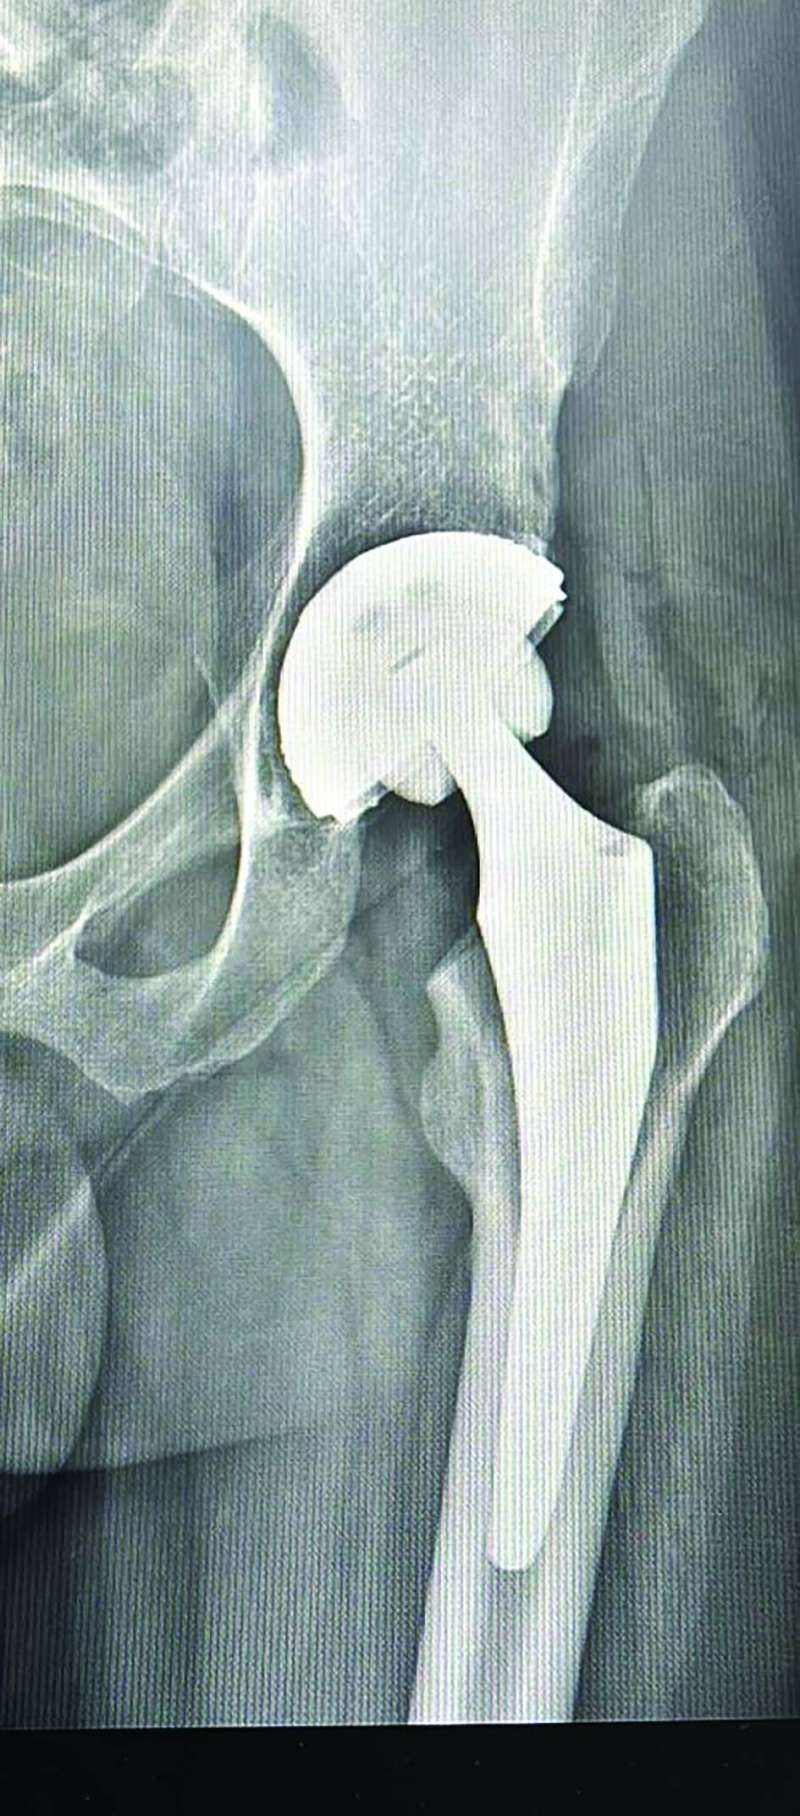

- هي عملية تغيير مفصل الورك لمريض شاب، كان يُعاني من مرض النخر العظمي، الذي يتم فيه فقدان وصول الدم الى مفصل الورك، ما يؤدي الى خشونة شديدة في بعض الحالات، وللأسف هذا ما وصل إليه هذا الشاب الذي عمره 35 سنة، وكما هو معلوم فليس من المتعارف عليه إجراء هذه العملية كعملية يومية، ولكن تحدثنا الى المريض، وكان القرار بإجرائها كعملية يومية، وهذا يحدث لأول مرة في مستشفى المواساة وعلى مستوى الكويت، وحتى على مستوى العالم هناك مراكز محددة تقوم بهذه العملية عبر جراحة اليوم الواحد.

-نستخدم خلال العملية بعض التقنيات الحديثة التي تؤدي إلى أن الآلام بعدها تكون معدومة تقريباً. كما كان المريض قادراً على المشي مباشرة بعد الإفاقة من التخدير، وهو بخلاف المتعارف عليه في مثل هذه النوعية العملية، حيث المريض قد يحتاج إلى يوم أو يومين لبدء العلاج الطبيعي ومن ثم المشي.

أوضح عاشوري، أن العملية استغرقت نحو ساعة فقط، مشيراً إلى أنه كلما كان وقت العملية أقصر، مع الالتزام بالإجراءات الفنية السليمة، كلما كانت نسبة النجاح أكبر.